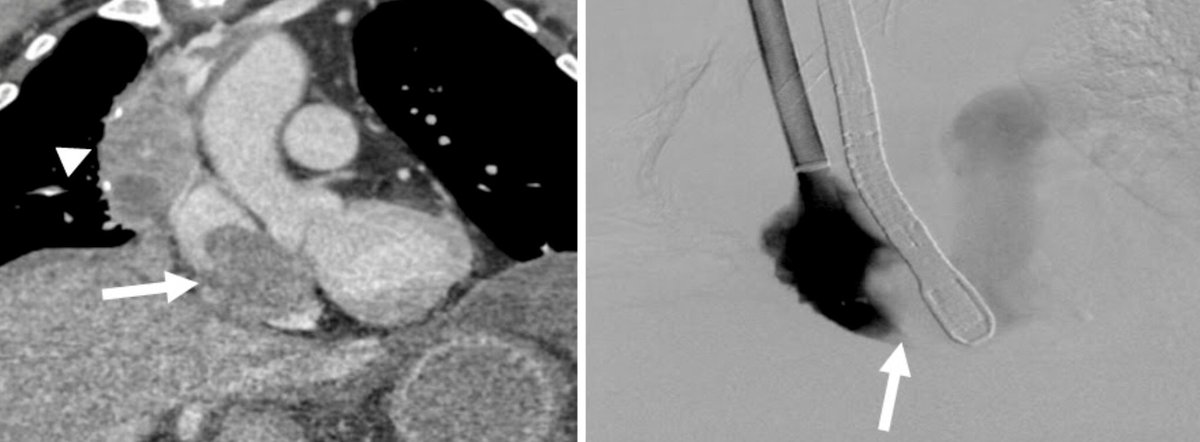

Right Atrial Thrombus??

Have no fear AngioVac is here! #IRAD#SingleSessionSuction#AngioVac#Venous Disease#WeAreIR@JonnyMoriarty@medravi@jhussainMD@EJJohnsonMD@iRadRaj@IRadNAP@KyleCooperMD@AlexCVIR@mmkhayatmd@JBundyRad@svmehtamd@JVIRmedia@_backtablepic.twitter.com/B7uNUrG8Vn